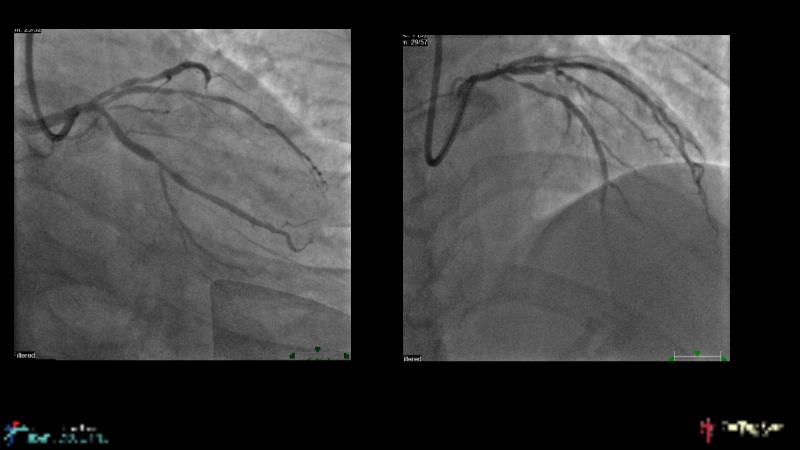

This session is recommended for you if you are seeking insights into the advantages of using IVUS imaging over visual assessment for better outcomes in left main bifurcation procedures. Discuss with experts the benefits of using RotaCUT in lesion preparation for left main bifurcation and explore the impact of high radial strength stents on the procedure's success.

• To understand why the use of IVUS imaging is different from seeing with experienced eyes to achieve improved left main bifurcation outcome